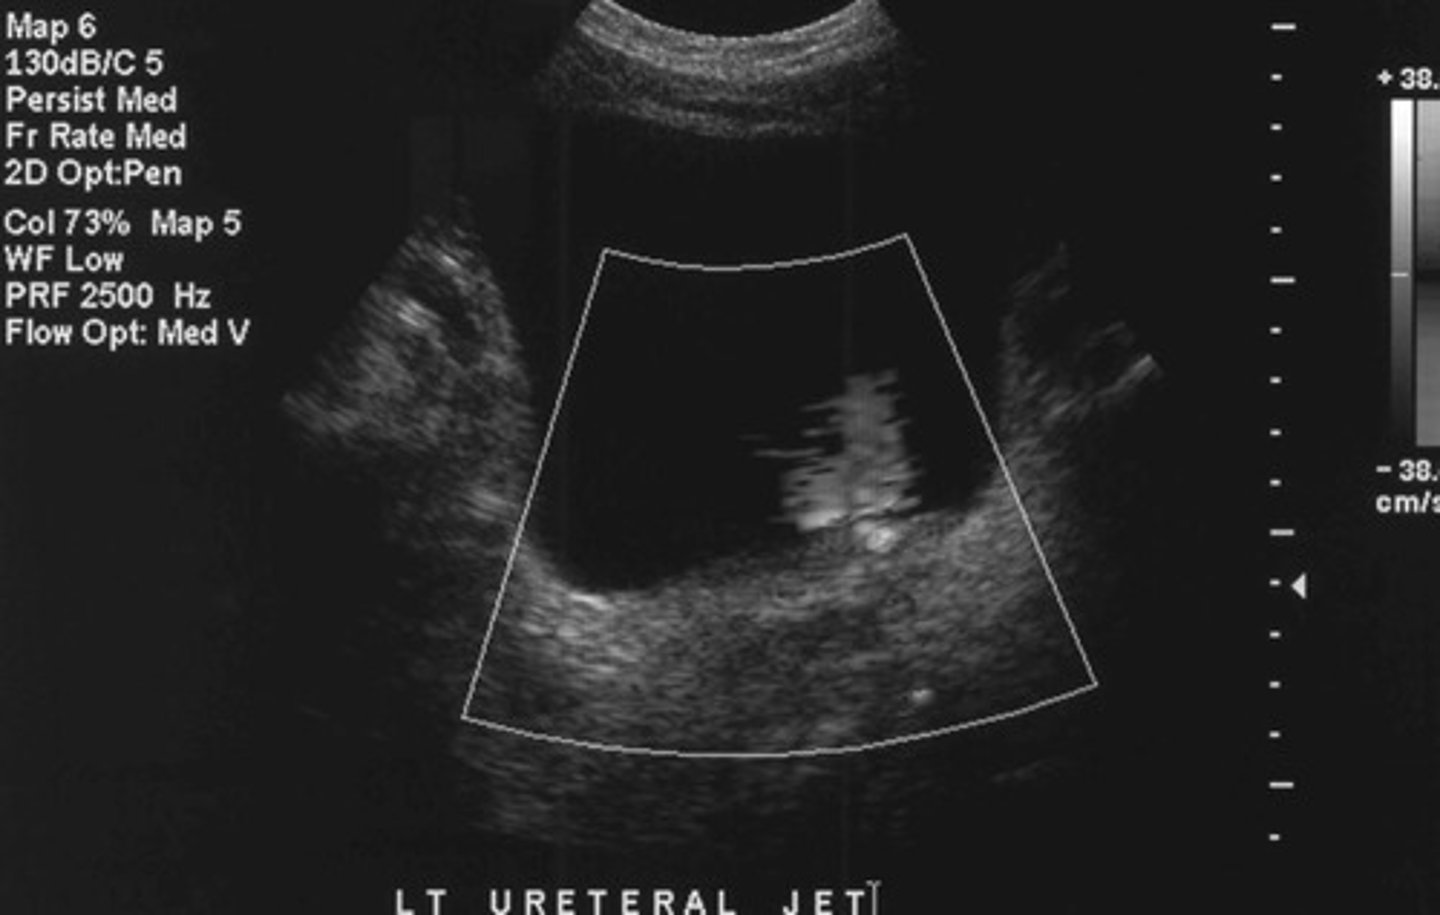

Want to determine if the stone is completely or just partially obstructing an ureter

Why do you ALWAYS want to asses a urine jet when you find a stone in the ureter

Urethral jet

What does this image show

Ureteral jets (is it fully or partially obstructive?)

What else should you assess if you identify obstructive hydro

The treatment/how fast we need to treat the patient (if fully obstructive may be more emergent)

Why do you need to determine if an obstruction in the collecting system is fully obstructive